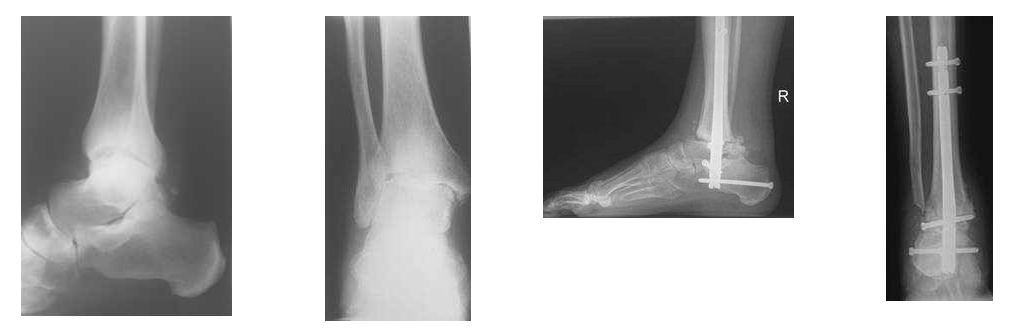

Mittel- und Rückfußchirurgie bei Arthrose

Bei Arthrosen des Mittel- und Rückfußes wird versucht, mit Einlagen und Schuhzurichtungen die Beschwerden zu beeinflussen. Führt dies nicht zur Linderung, so wird die operative Versteifung einzelner Gelenke durchgeführt. Die totalendoprothetische Versorgung des oberen Sprunggelenks wird ebenfalls in unserem Haus angeboten und stellt bei ausgewählten Indikationen (z.B. rheumatoider Arthritis) eine Therapieoption dar.